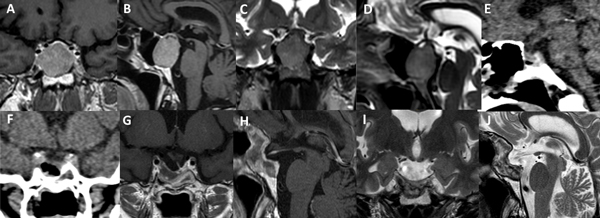

La técnica de “Guante Blanco” se indica en pacientes con macroadenomas no funcionantes, apoplejía pituitaria, enfermedad de Cushing, acromegalia, adenoma secretor de TSH y en portadores de prolactinomas con una clara indicación quirúrgica. La indicación principal es en tumores infradiafragmáticos, es decir, por debajo de la duramadre del diafragma selar o respetando el orificio del anillo dural (Figura 5). Se podría valorar a futuro su indicación en casos con extensión supraselar sin invasión ventricular y sin invasión lateral.

Figura 5. Paciente de 45 años con prolactinoma infradiafragmático resistente a cabergolina. Se utilizó un abordaje de Guante Blanco para su tratamiento. A-D: RM preoperatoria. E-F: TC del primer día postoperatorio. G-J: RM postoperatoria.